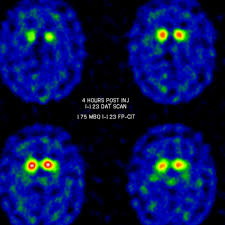

Dat scan parkinson disease. Update on treatments for the motor symptoms of Parkinsons disease published correction appears in. DaTSCAN which measures the density of nigrostriatial dopamine transporter sites may in some cases help the clinician make the correct diagnosis. Summary Systematic review to assess the diagnostic accuracy of DAT SPECT imaging which includes DaTSCAN.

DAT-SPECT results lead to changes in management and the outcomes of these changes are consistent with scan results. The DaTscan Ioflupane I 123 injection also known as phenyltropane is a radiopharmaceutical agent which is injected into a patients veins in a procedure referred to as SPECT imaging. Clinical diagnosis of Parkinson disease PD was certain in 26 and uncertain in 31 patients.

Inclusion criteria required clinical diagnosis of Parkinsons or clinically uncertain parkinsonism and. Dopamine transporter DAT-scan has high sensitivity and specificity to differentiate patients with parkinsonian syndromes Parkinsons disease multiple system atrophy and progressive supranuclear palsy from essential tremor and healthy control. International Parkinson and Movement Disorder Society evidence-based medicine review.